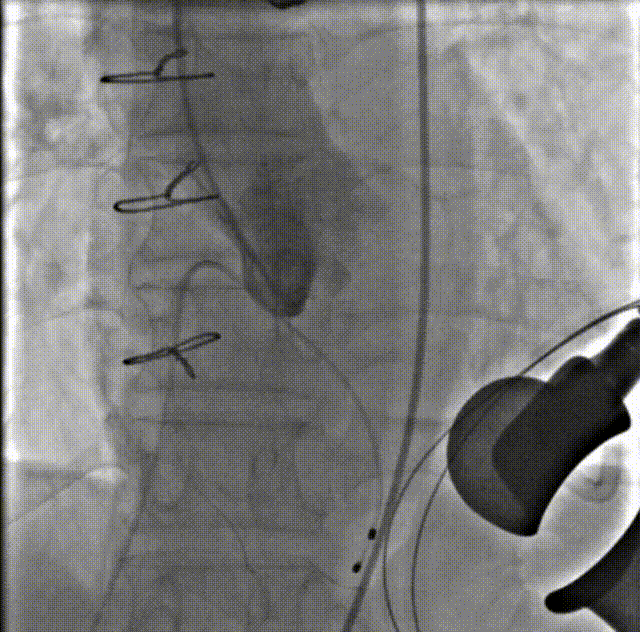

术前造影

瓣膜仓入位

瓣膜仓打开